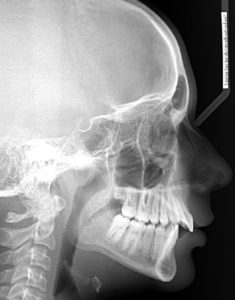

A 12 year old Caucasian male presents with a chief concern that “I don’t like my overbite”